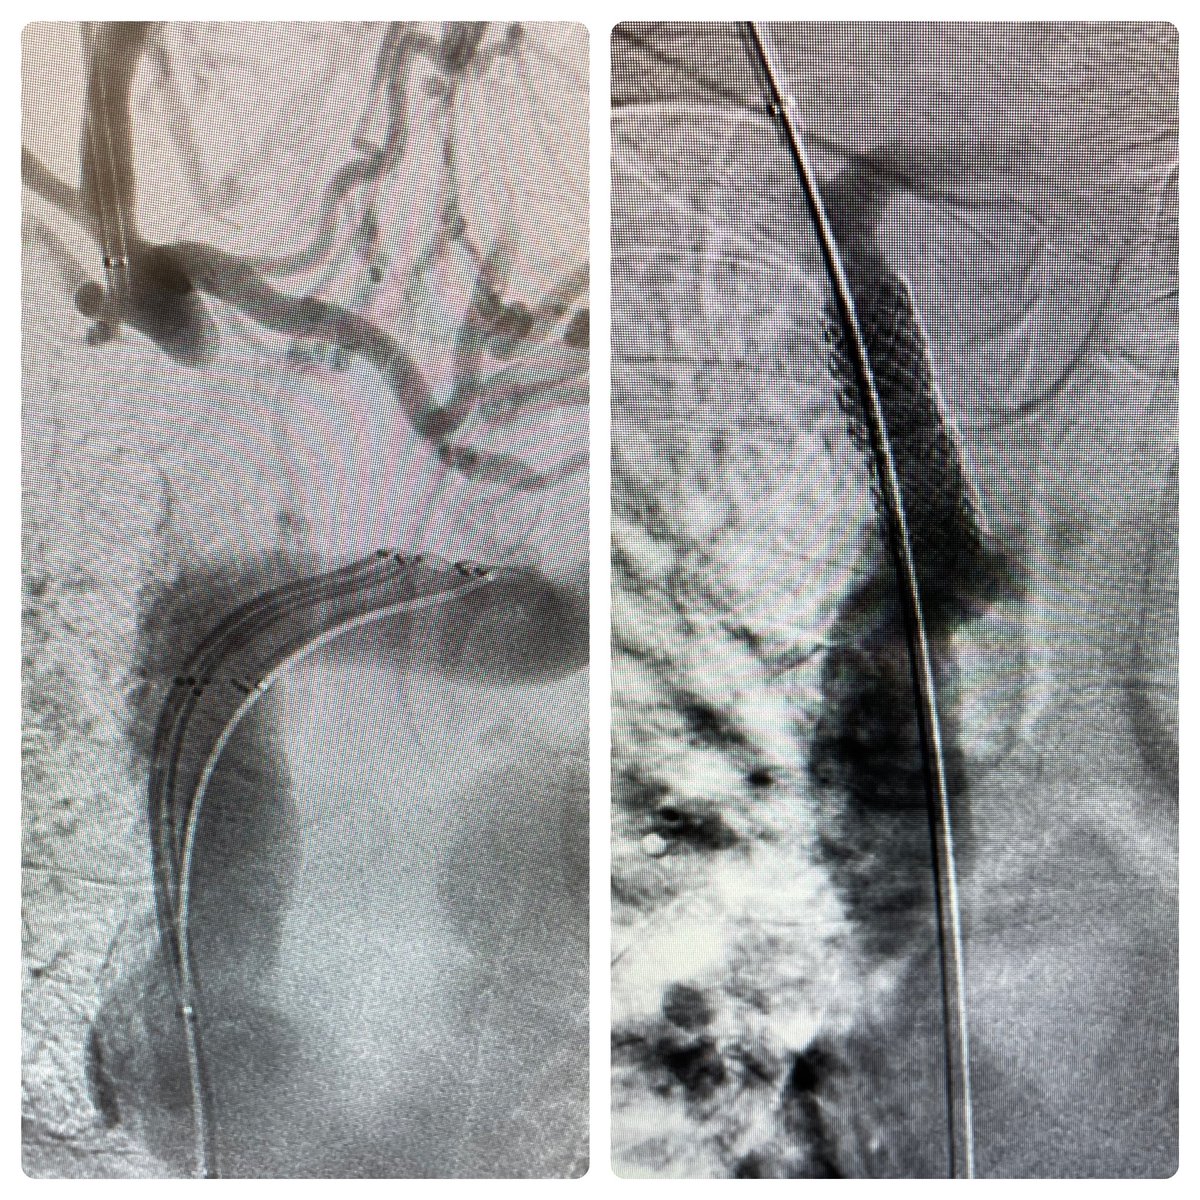

Patient with facial swelling and difficulty breathing. I called in my friends BRK, amplatzer 1, and V18. They helped cross the chronic occlusion. My old confidant the Z-stent then paved the way. Next day, swelling resolved and breathing normal.

Hot take: there are no uncrossable venous occlusions. Don’t condemn patients to a lifetime of femoral tunneled catheters or debilitating face and arm swelling without referring first to centers with appropriate equipment and experience to get these vessels open. #irad Loma Linda U. Health

Hot take: there are no uncrossable venous occlusions.

Don’t condemn patients to a lifetime of femoral tunneled catheters or debilitating face and arm swelling without referring first to centers with appropriate equipment and experience to get these vessels open. #irad <a href="/LLUHealth/">Loma Linda U. Health</a>